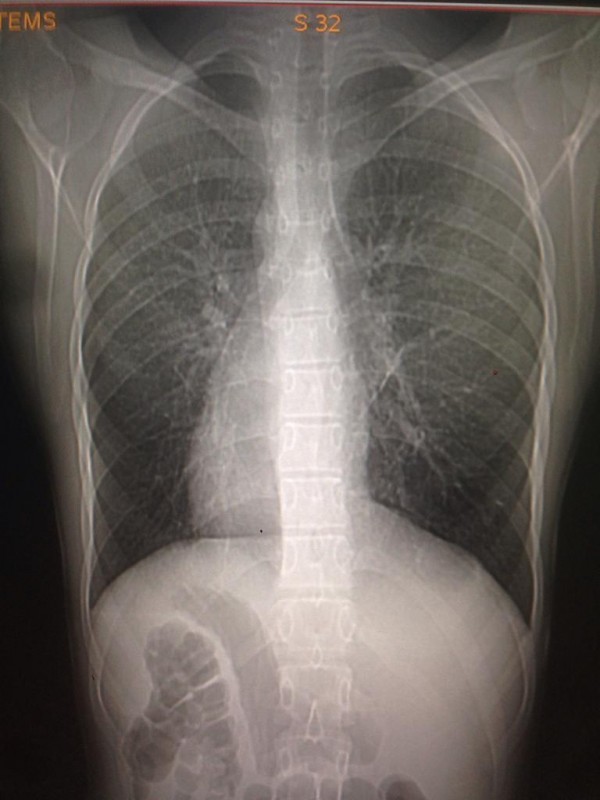

Транспозиция внутренних органов - редкий вариант биологически нормальной анатомии, в котором основные внутренние органы имеют зеркальное расположение по сравнению с обычным нормальным положением: сердце - справа, печень - слева, желудок - справа. Такой случай встречается у одного человека из 10 тысяч. Главная причина - мутация генов, и передается аномалия по наследству.

Транспозиция внутренних органов. Снимок предоставлен Сундетом Саргеловым

К сожалению, точных статистических данных обо всех казахстанцах, сердце которых расположено с правой стороны грудной клетки, нет. Однако, по словам медработника, в нашей стране ситуация аналогична мировой. Таким образом, если население Казахстана в среднем составляет 18 миллионов, то по вычету получается, что среди нас живет около 1800 правосердечников. В основном люди узнают об аномалии, когда делают рентген. К тому же зачастую посмертное вскрытие не проводят, так как родные умершего бывают против этой процедуры.